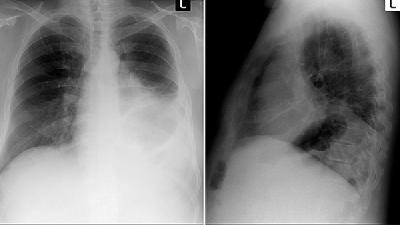

首先我們要對(duì)急性肺炎有一定的了解,這是一種比較罕見(jiàn)的發(fā)展迅速的爆發(fā)性肺損傷,是肺部的急性損傷性病變?;颊咂鸩?huì)非常突然,主要表現(xiàn)為發(fā)熱、咳嗽、氣急、呼吸衰竭,繼發(fā)感染之后可能還會(huì)引發(fā)胸悶、乏力、呼吸困難等多種不適癥狀。醫(yī)學(xué)人員認(rèn)為這種病的發(fā)病原因跟患者感染急性病毒有一定的關(guān)聯(lián)。

那么到底急性肺炎能治愈嗎?肺炎的起病原因因?yàn)橛泻芏喾N,所以醫(yī)學(xué)上根據(jù)發(fā)病原因?qū)㈤g質(zhì)性肺炎分為六種,每一種肺炎的治療效果,生存時(shí)間都不一樣。

所以急性肺炎能不能治愈,需要大家去醫(yī)院做具體的檢查,看看是哪一種類型的急性肺炎,醫(yī)生會(huì)根據(jù)患者的具體病況來(lái)判斷應(yīng)該如何治療。如果大家還有更多的疑問(wèn),最好能夠去專業(yè)正規(guī)的醫(yī)院咨詢專家。